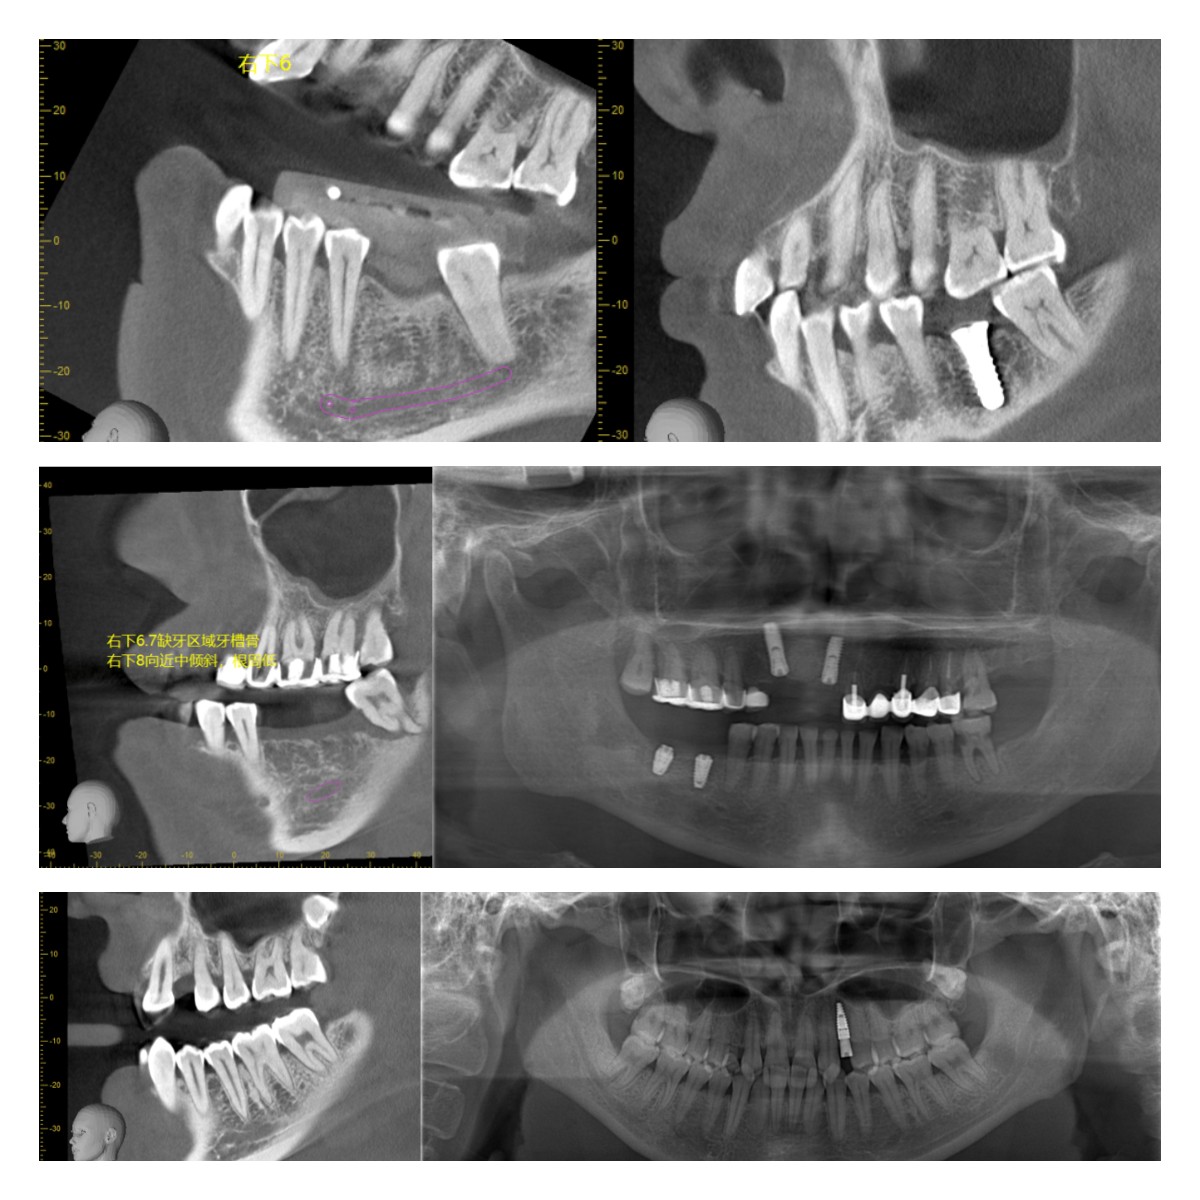

部分病例展示: